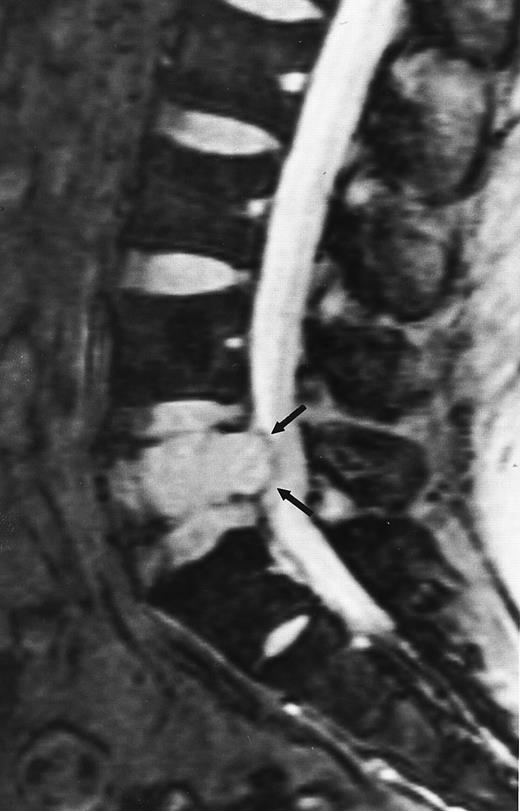

T1-weighted (500/11, TR/TE) sagittal MR images of the lumbosacral spine in a 45-year-old woman before (A) and 40 days after (B) bone marrow transplantation for multiple myeloma. There is a diffuse MR pattern of marrow involvement in (A) (bone marrow plasma cells, 50%; monoclonal protein, 6.0 g/dL). On the posttreatment image, there is definite reinstitution of fatty marrow in the spine and, in particular, around the basivertebral veins, in keeping with partial response to treatment (bone marrow plasma cells, 0.5%; monoclonal protein, 1.6 g/dL).